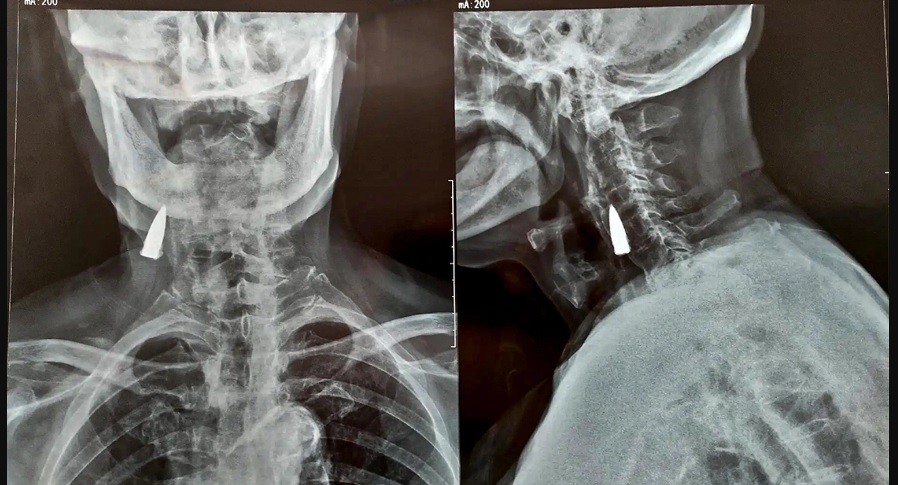

Un hombre de 95 años descubrió que tenía una bala incrustada en el cuello al sentir malestar en la zona y realizarse una tomografía.

De acuerdo con Wang, yerno de Zhao, le realizaron la la radiografía a raíz de una caída accidental que sufrió el hombre en su balcón de su domicilio.

No se sabe con exactitud cómo es que la bala llegó hasta su cuello y quedó cerca de vasos sanguíneos, debajo de la mandíbula.

Pese a que podría someterse a una operación para extraer el elemento, la familia y el equipo médico han desistido, puesto que sería un riesgo para el veterano.